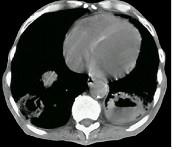

问题 女,52岁,曾患有鼻窦炎,最近发现咳嗽发热,影像学检查如图,最可能的诊断为 ( )

选项 A.多发性肺脓肿 B.浸润型肺结核并空洞形成 C.韦格肉芽肿 D.结节病 E.肺转移瘤

答案 C